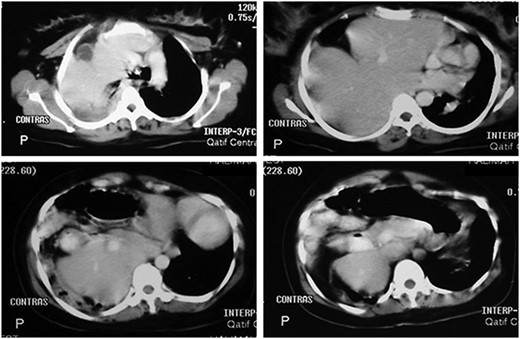

Abdominal CT scan with contrast showing the entire liver and some bowel loops occupying the right hemi-thorax.

showed the entire liver and some bowel loops in the right hemi-thorax (Fig. 2). The impression was right diaphragmatic herniation, although ruptured right hemidiaphragm was entertained despite the negative history of chest trauma.